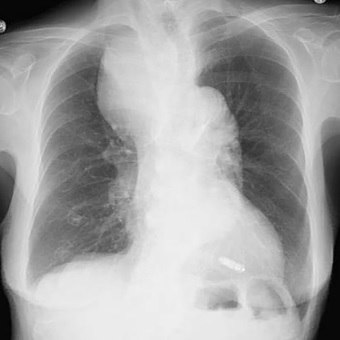

Pulmonary vein stenosis requiring angioplasty or surgical treatment following pulmonary vein isolation: case series

心房細動に対する肺静脈隔離術後に肺静脈狭窄を来たし肺静脈ステント留置または外科的肺葉切除を要した3症例:ケースシリーズ

Haruka Iwama/岩間 春佳

肺静脈狭窄は肺静脈隔離術後の合併症として稀ではあるが発症した際には侵襲度の高い治療を要する重篤な病態である。当院で直近に経験した3症例は①複数回の高周波治療、②1回の高出力短時間焼灼セッティングでの高周波治療、③クライオバルーン治療→高周波治療、という異なる治療歴を持っており、治療としても肺静脈ステント治療または外科的肺葉切除を行っている。その多岐に渡る症候性、病態、治療へのアプローチは肺静脈狭窄を理解する一助になると考える。

当院で経験した3症例は肺静脈狭窄に至る治療歴や患者背景、症状の有無、治療選択肢がそれぞれ異なっており肺静脈狭窄という病態の認識と理解、対応について多くの知見を得させて頂きました。アブレーションに関わっていなくとも肺静脈隔離術が一般化した治療となった現在では外来において遭遇する可能性もある病態であり肺静脈狭窄を気づくきっかけになればと思います。